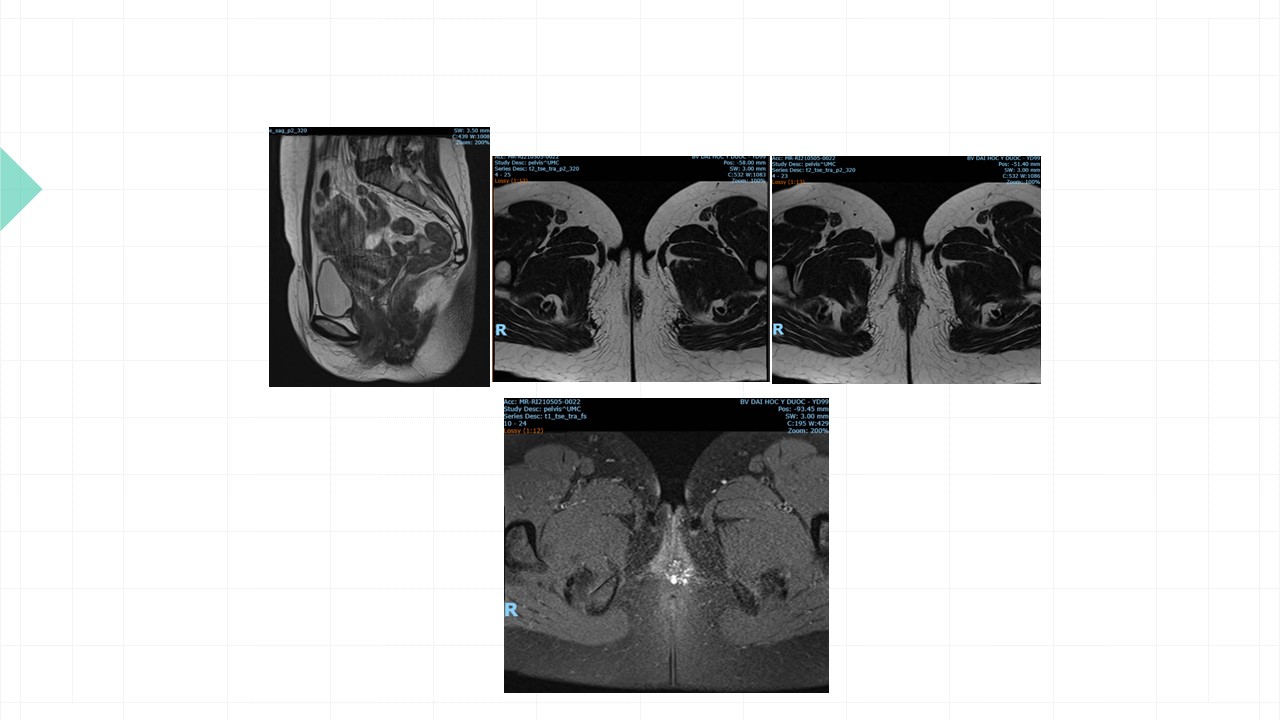

Vai trò cộng hưởng từ trong đánh giá lạc nội mạc tử cung

Từ khóa: Vai trò cộng hưởng từ trong đánh giá lạc nội mạc tử cung